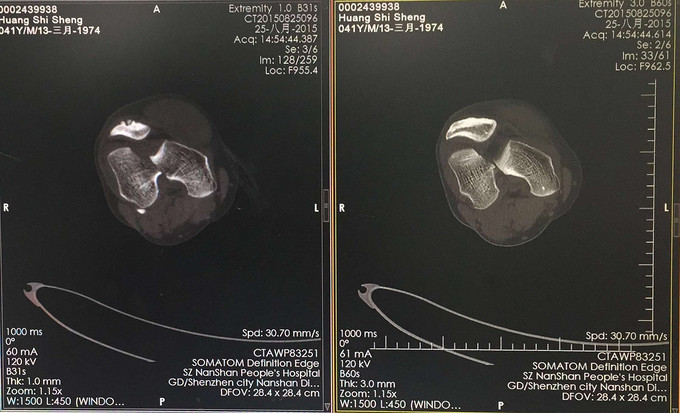

查体:右大腿中下段短缩成角畸形,肿胀,可扪及骨擦感,患肢末梢感觉血运可。 X:右股骨下端骨折 CT:右股骨下端骨折,波及关节面。

右股骨远端粉碎性骨折 完善检查,行右股骨远端骨折切开复位内固定术。